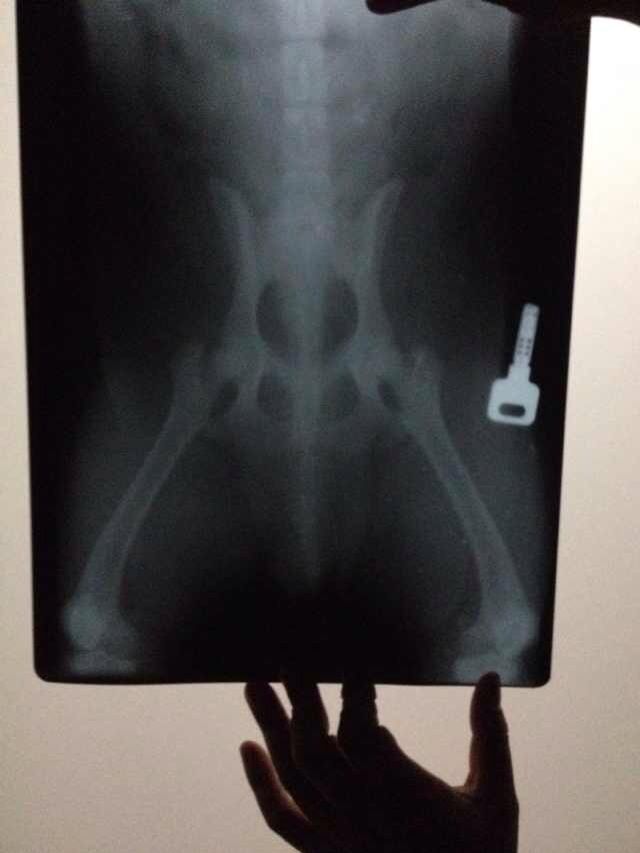

我家狗发生这种症状了,突然感觉后腿无力,站起来有点费劲,家里地板是瓷片有点滑,但是以前从来没有过这种现象,我总结了最近这几天的历程,第一点,有天和一只大狗玩,那只大狗骑我家狗骑了快一个小时,我家狗想反抗但是老是后腿被压住想站站不起来,第二点,有天上乒乓球案子直接跳上去了以前没跳过这么高的,第三点,有天洗澡好像腿上的毛没吹干。昨天去医院拍了三张片子,骨头没事,医生给我说它的髋关节有点薄我也不是很懂,医生让我买保健品叫康仕得,一瓶75粒能吃一个月,六百多块钱,我觉得有点贵没买医生还感觉不太高兴的样子,在这我想问问大家伙,谁家狗出现过这种情况,现在应该怎么办?